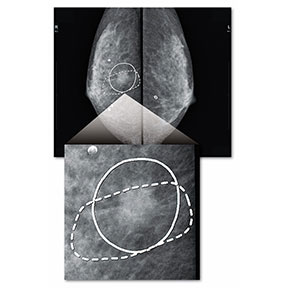

Breast Density Assessment (Bda)

精中機構ガイドライン*に沿った解析アルゴリズムで乳房構成(乳腺密度)を自動的に判定する画像処理です。

従来は人間が主観的に評価・分類していた乳房構成を、客観的で再現性に優れた判定結果として提示することで、マンモグラフィー検診画像の読影を強力にサポートします。

* 特定非営利活動法人日本乳がん検診精度管理中央機構「乳房構成の判定方法」(2020年2月6日)

マンモグラフィー診断支援ソフトウェアMGCAD-i

独自のアルゴリズムに基づくマンモグラフィー診断支援ソフトウェアです。マンモグラフィー検診画像の「見落とし防止」や「読影時間の短縮」を強力にサポートします。